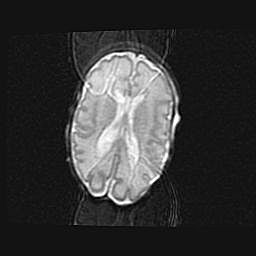

Наружная гидроцефалия с возможной атрофией височных областей.

Возраст: 28 дней

Вес: 3670 г

Пол: мужской

Окружность головы: 38 см

Срок гестации: 40 недель

Гидроцефалия головного мозга у новорожденных – это заболевание, которое характеризуется скоплением избыточного количества спинномозговой жидкости в желудочковой системе головного мозга в результате затруднения её перемещения от места выработки к месту поглощения в кровеносную систему или вследствие нарушения абсорбции. При открытой наружной форме гидроцефалии у новорожденных расширяются и переполняются субарахноидные пространства.

При нормотензивных  формах,  которые,  как  правило,  являются  следствием  перенесенных ишемических  повреждений  паренхимы  мозга,  возможно  сочетание микроцефалии  с нормотензивной гидроцефалией. В основе данных изменений лежит атрофия больших полушарий с преимущественной  локализацией  в  лобно-височных  областях.